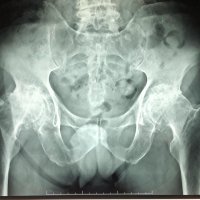

BILATERAL HIP PAIN

M, 77 y.o, with bilateral hip pain.

Anteroposterior pelvis radiograph reveals complete obliteration of bilateral hip joints space with associated marginal osteophyte, subchondral sclerosis and cyst formation, also deformity of femoral heads and acetabulum, in keeping with severe osteoarthritis of the hips.

An asphericity of the femoral heads with osseous “bump” formation at the anterolateral femoral head-neck junction just lateral to the physeal scar is also noted, consistent with cam deformity.

This asphericity leads to unwanted force transmission to the acetabulum during flexion and internal rotation, leading to wear and tear of the labrum dan cartilage, and subsequently resulting in degenerative joint disease.

Cam deformity is usually causes by a primary osseous variant of the head-neck junction, but it also can be the result of several known etiologies include malunion of a femoral neck fracture, slipped capital femoral epiphysis, developmental dysplasia of the hip, or Legg-Calve-Perthes’ disease.

Courtesy of Dr. dr. Elysanti Dwi Martadiani, Sp.Rad(K)